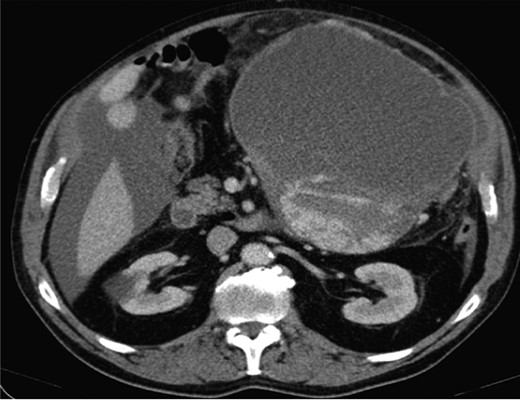

Computed topography (CT) of the chest, abdomen and pelvis reported a large mass predominantly cystic with more confluent solid-enhancing components and septation inferiorly and posteriorly measuring 21.7 cm (antero-posterior) × 16.3 cm (transverse) × 20.5 cm (infero-superior) in the upper abdomen. The mass appeared separate from the pancreas displacing small bowel loops with the lateral margin of the mass in contact and displacing the descending colon (Fig. 1).